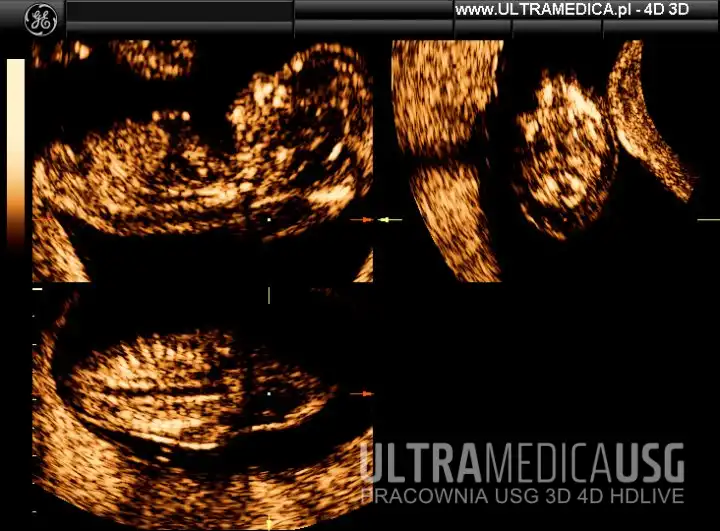

Badania USG ciąży 1 trymestru – filmy i zdjęcia

Przykładowe obrazy i filmy z badań I trymestru ciąży:

Film: USG ciąży 1 trymestr - kości nosowe płodu - USG 3D

Film: USG ciąży 1 trymestr - pomiar NT w technologi VCI-A - USG 4D

Film: Płód w 11. tygodniu ciąży - USG 4D